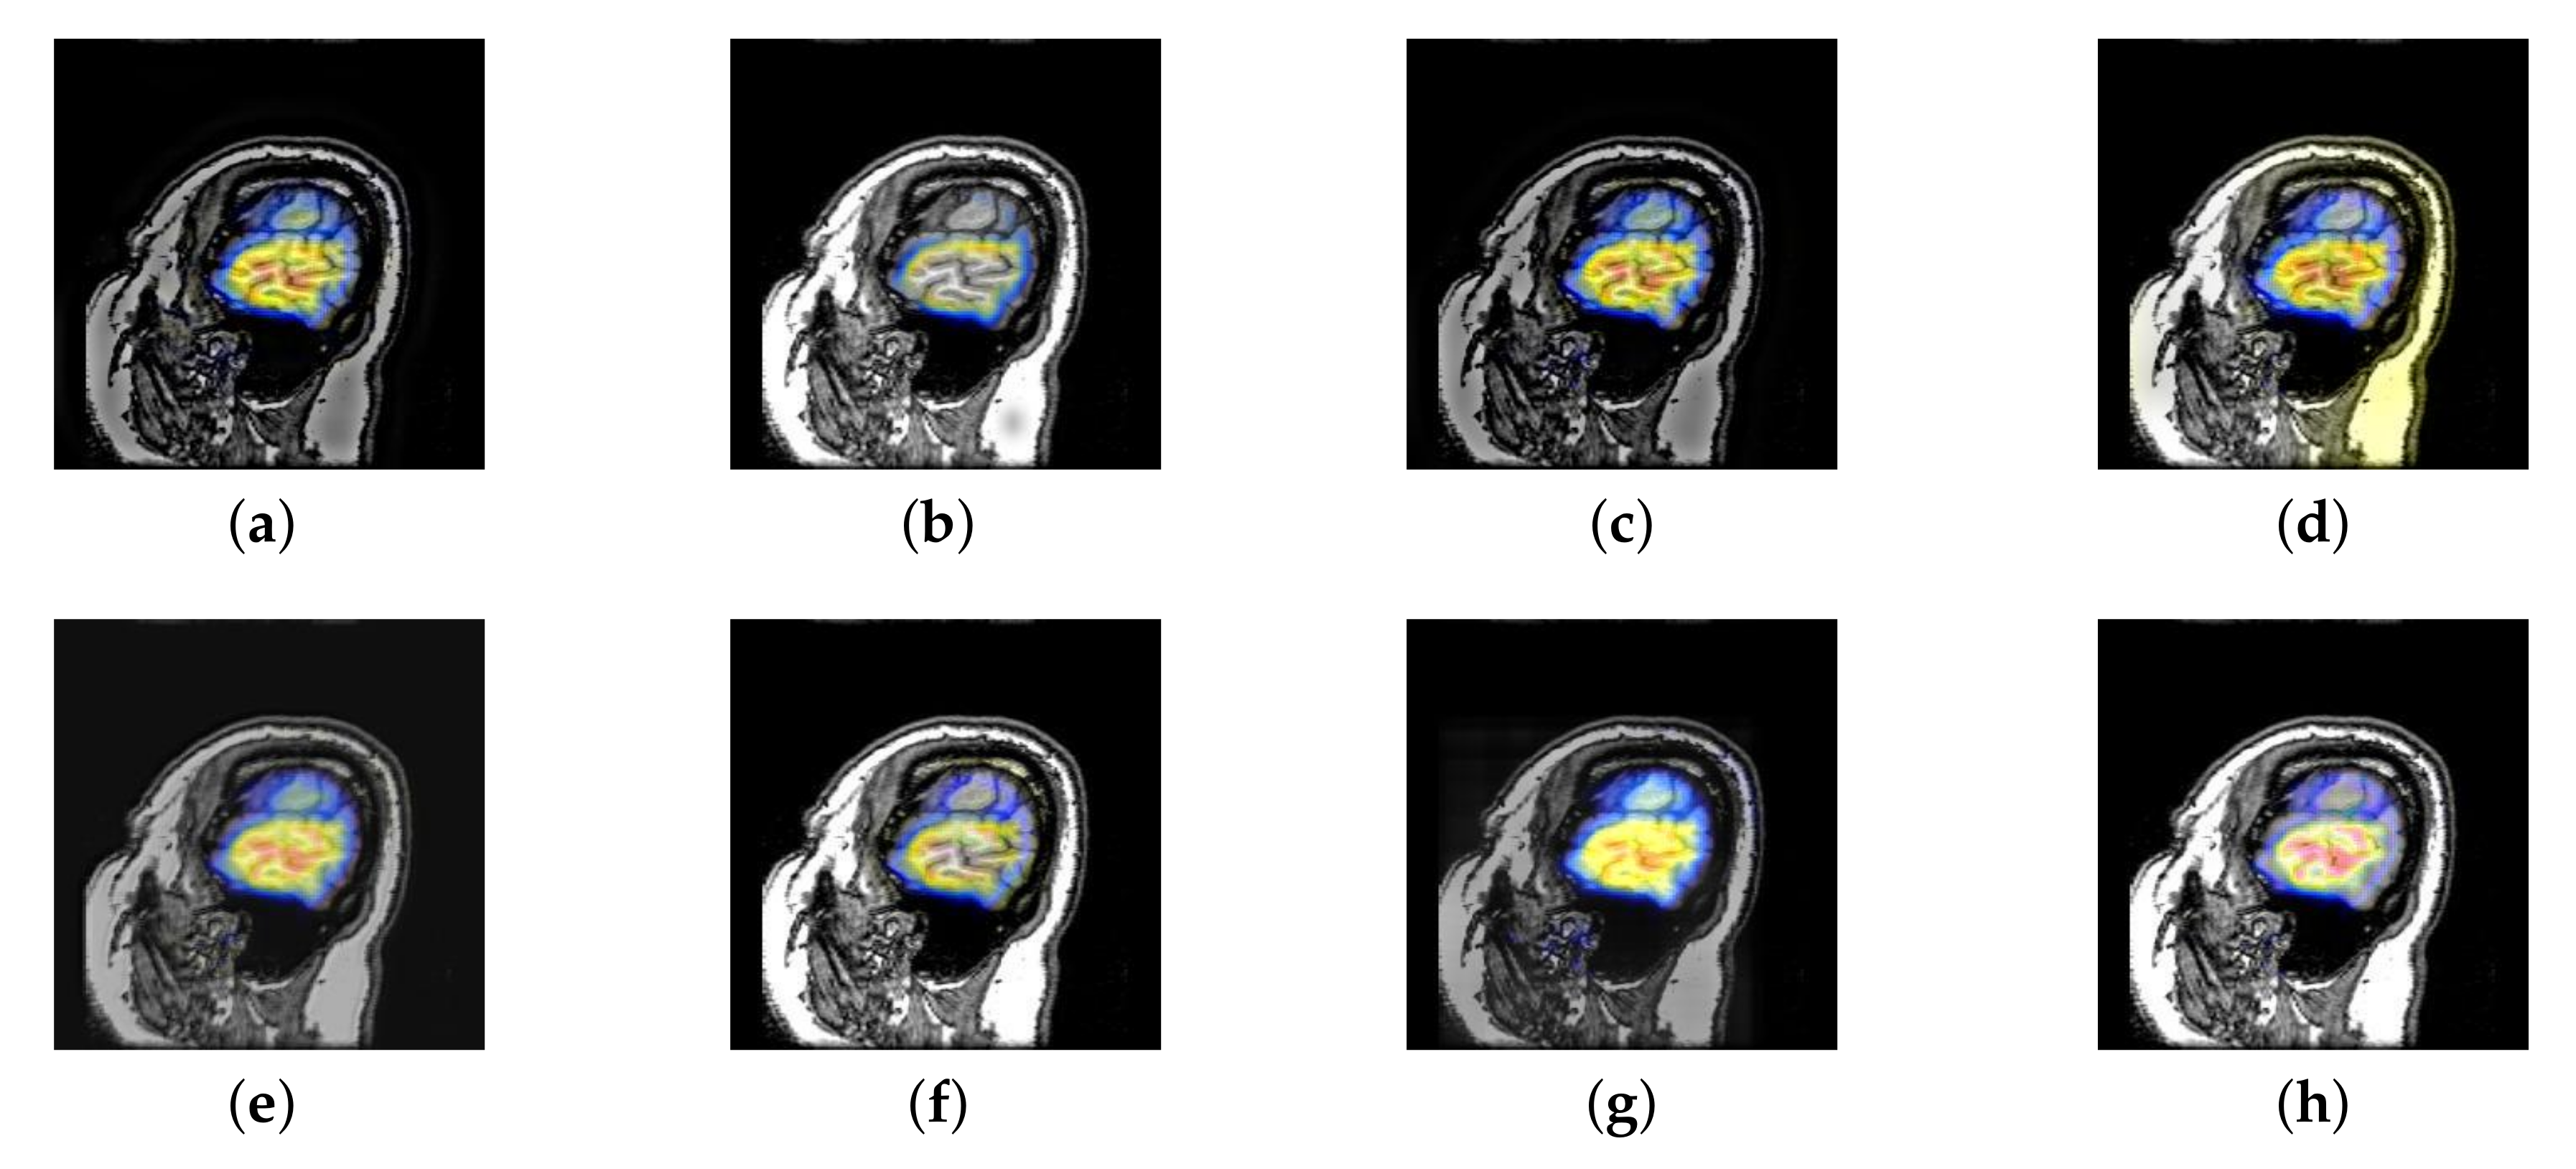

In this section, all FDG images are derived from the normal human brain, but the angle is chosen differently in Figure 24. In Figure 25, Figure 26, Figure 27 and Figure 28, we find that the color information obtained by the image fusion method based on NSCT, DTCWT, and LPSR is better preserved, but the structure information is lost more. The fusion image based on GFF, IGM, and FusionCNN method retains the complete structure information in the MRI image, but the color obtained from the FDG image is distorted. The image color information obtained by DDcGAN fusion method is too bright, resulting in unclear color area details and low contrast of color region. In contrast, the image obtained by our algorithm has moderate brightness of color information, complete structure information, and complete biological detail information.

Figure 25.

Fused medical images obtained by different algorithms (Figure 24a,b): (a) DTCWT, (b) GFF, (c) NSCT, (d) LPSR, (e) IGM, (f) FusionCNN, (g) DDcGAN, and (h) FusionNet.

Figure 26.

Fused medical images obtained by different algorithms (Figure 24c,d): (a) DTCWT, (b) GFF, (c) NSCT, (d) LPSR, (e) IGM, (f) FusionCNN, (g) DDcGAN, and (h) FusionNet.

Figure 27.

Fused medical images obtained by different algorithms (Figure 24e,f): (a) DTCWT, (b) GFF, (c) NSCT, (d) LPSR, (e) IGM, (f) FusionCNN, (g) DDcGAN, and (h) FusionNet.

Figure 28.

Fused medical images obtained by different algorithms (Figure 24g,h): (a) DTCWT, (b) GFF, (c) NSCT, (d) LPSR, (e) IGM, (f) FusionCNN, (g) DDcGAN, and (h) FusionNet.